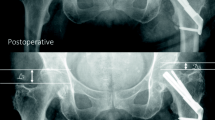

Patients were hospitalized for a mean of 4 days (SD 2.8 days). Five patients were hospitalized over 7 days due to unavailable rehabilitation places, but were clinically ready for hospital discharge after 4 days. One patient developed pneumonia and an urinary tract infection postoperatively which were both successfully treated using antibiotics. No intra-operative complications were observed. Eight patients (23.5%) presented themselves within 12 months due to persisting pain in the affected hip. In six of these patients, additional radiological imaging showed both biological failure, namely, avascular necrosis (n = 4), and implant failure, defined as cut out (collaps of the neck–shaft angel into varus) (n = 2). Two out of these eight patients showed no radiological abnormalities in fracture healing after 8 months but complained of the sensation of irritating osteosynthesis material. In these two patients, implants were removed 10 months after primary surgery and both patients rehabilitated uneventful after removal without further pain during follow-up. These patients were not included in the failure group as no clinical or radiological cause for their complaints could be found. With regard to the failure of osteosyntheses, four out of six cases had suboptimal implant positioning (increased tip–apex distance or the implant not centrally positioned, see (Fig. 3)). In those cases, 3 patients showed avascular necrosis, one cut-out. All six patients with CRIF failure underwent conversion to total hip arthroplasty. No additional interventions were required. No factors were found to significantly increase the risk for complications (see Table 2).